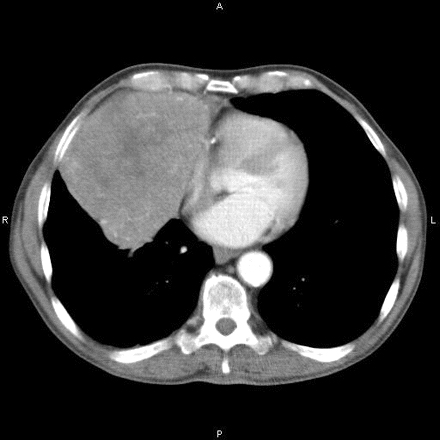

Tomografía computarizada que muestra una masa mediastínica anterior

Hamid UI, Jones JM. Masa mediastínica. BMJ Case Reports 2010 Oct 4;2010:bcr1120092471.